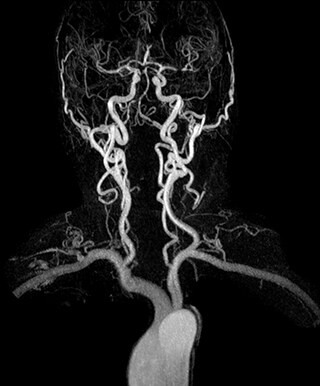

3D dynamic MRA of head and neck. Excellent image quality is obtained in this dynamic scan. Cor 3D T2, C-SENSE factor 5.4, scan time is 1:20 min, voxel size is 0.8 x 0.8 x 1.6 mm. Ingenia Ambition 1.5T.